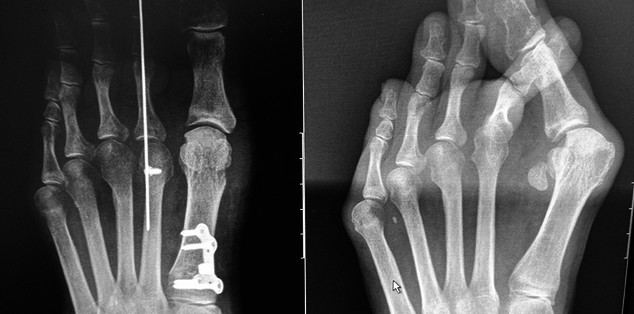

The experience for the foot and ankle fellow at the Rothman Orthopaedic Institute is second to none. As a Foot and Ankle division, we see approximately 40,000 patients and perform over 3,000 procedures annually. All areas of foot and ankle are covered and the benefit of our high volume can be seen with how comfortable our fellows become, even with rare and challenging surgical scenarios. As a division we perform over 160 total ankle replacements per year and are actively engaged in the design, development and improvement of these devices.